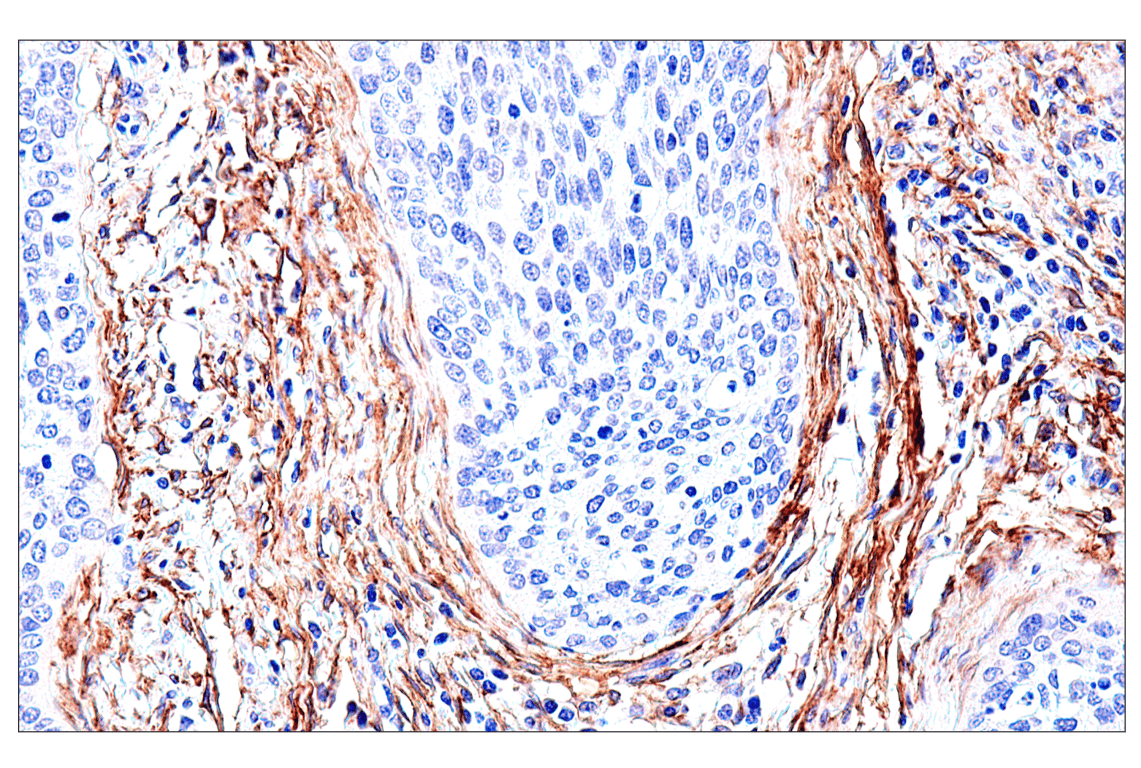

Immunohistochemical analysis of paraffin-embedded human uterine rhabdomyosarcoma using FAP (F1A4G) Rabbit mAb. Data were generated using the standard formulation of this product.

Immunohistochemistry Image 2: FAP (F1A4G) Rabbit Monoclonal Antibody (BSA and Azide Free)